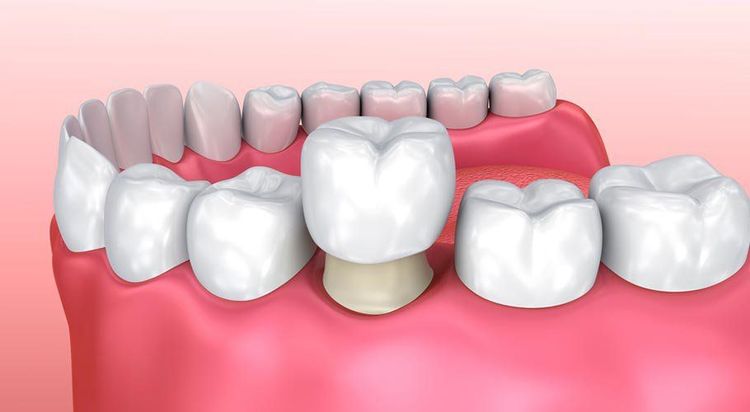

- Tùy thuộc vào phần tổ chức cứng còn lại nhiều hay ít, nha sĩ sẽ tái tạo lại thân răng để làm cho răng khỏe hơn khi mang răng sứ ở bên ngoài.

- Bước cuối cùng là làm chụp răng sứ ở bên ngoài vừa để bảo vệ phần răng bên trong vừa để đảm bảo chức năng ăn nhai và thẩm mỹ.